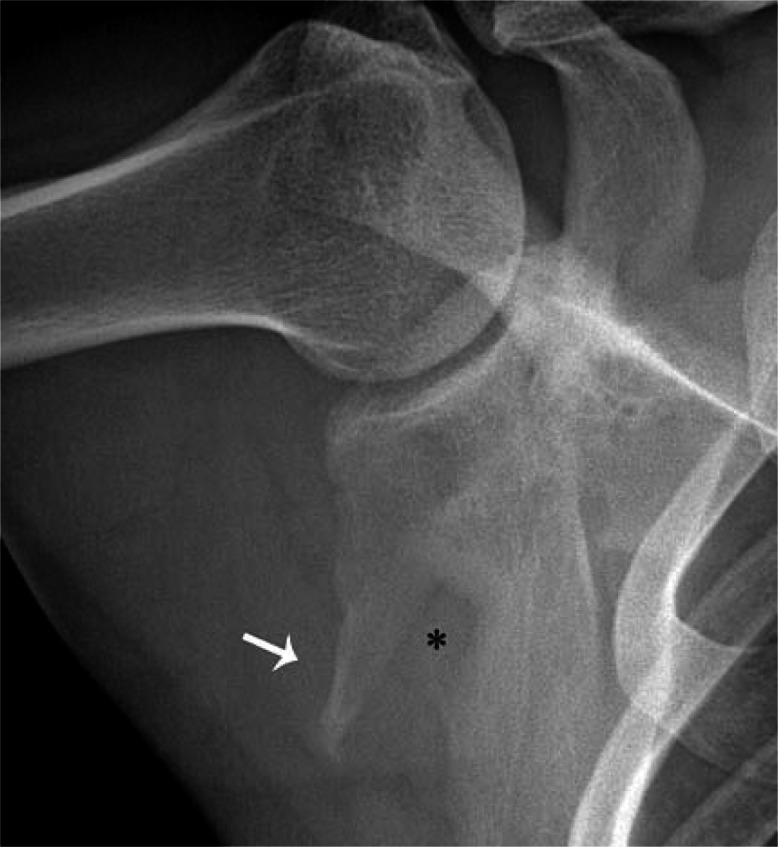

Figure 3D:

A serial radiograph of the shoulder obtained in abduction and external rotation 6 years after the injury reveals complete healing of the fractures with significant malunion consisting of a 4 cm long triangular subglenoid fragment (white arrow) and a persistent defect in the axillary border of the scapula (*)